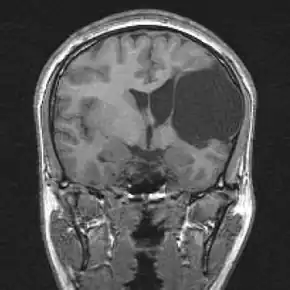

| Porencephalic cyst in the left parietooccipital and right frontal area.[1] | |

Porencephaly is an extremely rare cephalic disorder involving encephalomalacia.[2] It is a neurological disorder of the central nervous system characterized by cysts or cavities within the cerebral hemisphere.[3] Porencephaly was termed by Heschl in 1859 to describe a cavity in the human brain.[4] Derived from Greek roots, the word porencephaly means 'holes in the brain'.[5] The cysts and cavities (cystic brain lesions) are more likely to be the result of destructive (encephaloclastic) cause, but can also be from abnormal development (malformative), direct damage, inflammation, or hemorrhage.[6] The cysts and cavities cause a wide range of physiological, physical, and neurological symptoms.[7] Depending on the patient, this disorder may cause only minor neurological problems, without any disruption of intelligence, while others may be severely disabled or face death before the second decade of their lives. However, this disorder is far more common within infants, and porencephaly can occur both before or after birth.[3]

Cysts or cavities can occur anywhere within the brain and the locations of these cysts depend highly on the patient. Cysts can develop in the frontal lobe, parietal lobe, forebrain, hindbrain, temporal lobe, or virtually anywhere in the cerebral hemisphere.[8]